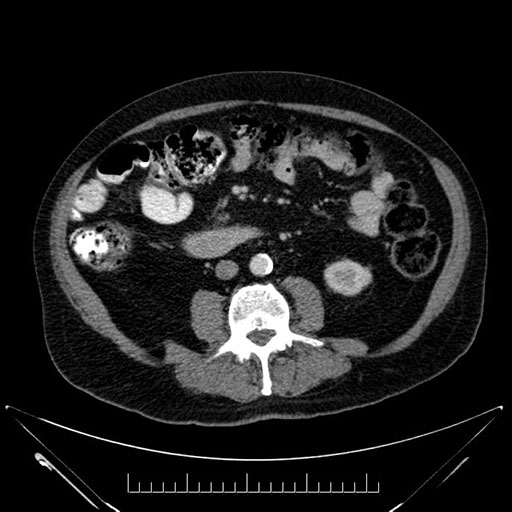

Whipple (pancreaticoduodenectomy) [case 7]

Imaging Analysis

Look through the patient's CT scan to identify any areas of concern for the necessary procedure.

Based on your CT findings, which issue(s) would give reason for "planned slowing down moment(s)" in this case?

Considering a standard Whipple procedure, what step(s) of the operation would you do differently in this case?